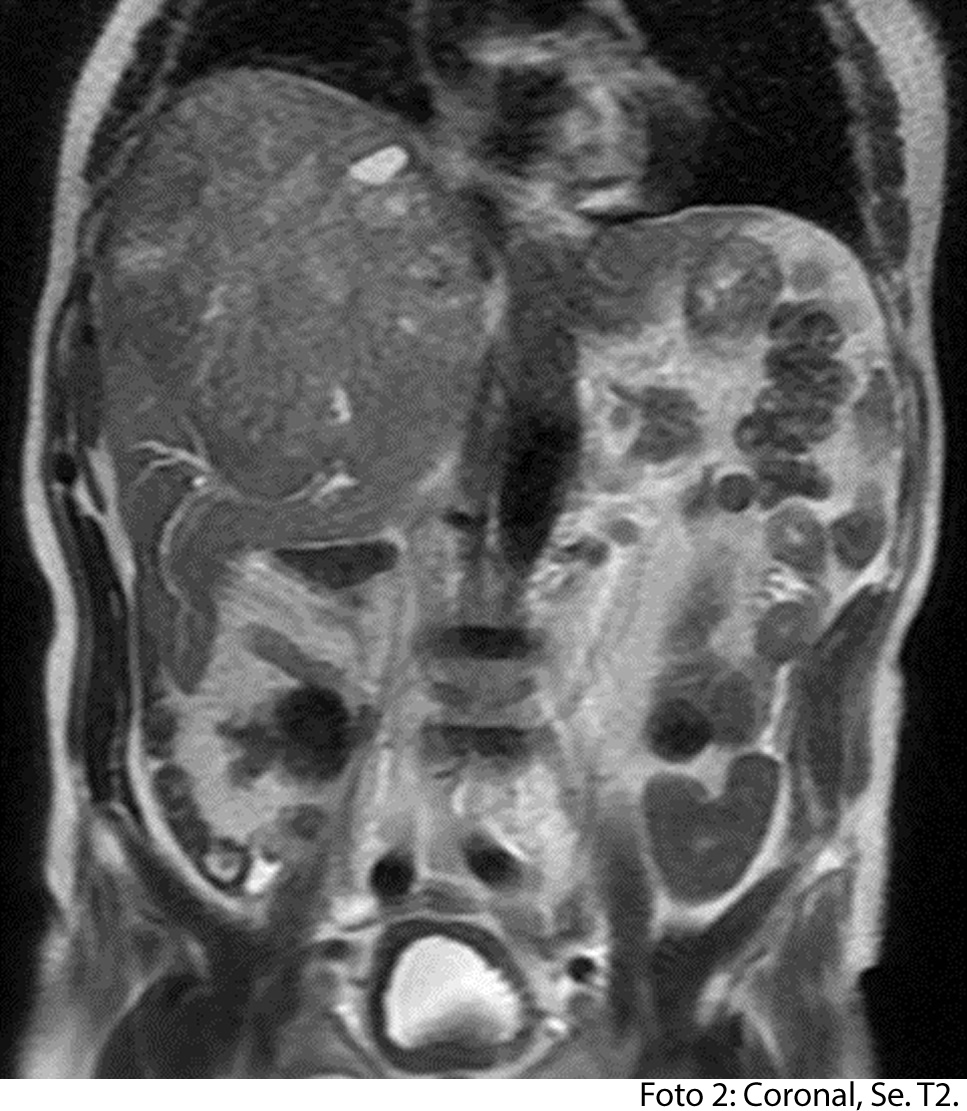

TECNICA EMPLEADA

Se procede a atender a paciente luego de cumplir con los protocolos para la realización de estudios de resonancia, paciente ingresa a zona 4, se coloca en posición decúbito supino, se utiliza gating respiratorio, estudio se obtiene con uso de bobina phase arrays, PSP Axial, sagital y coronal, secuencias Se y Gre, ponderadas a T1 y T2, se administra medio de contraste hepato especifico y se utiliza protocolo para estudio dinámico.

HALLAZGOS IMAGENOLOGICOS

• HEPATOCARCINOMA FIBROLAMINAL QUE COMPROMETE TODO EL LÓBULO DERECHO DEL HÍGADO

Es un método utilizado en el cual podemos observar una gran masa localizada en los segmentos del hígado también se puede medir el diámetro de la masa, el hepatocarcinoma también puede presentar focos hemorrágicos y además podemos captar de manera heterogénea el medio de contraste intravenoso. En los hepatocarcinomas podemos ver obstruyendo parcialmente la vena porta. Adenomegalias los cuales nos indican Los hallazgos como primera posibilidad diagnóstica, carcinoma hepatocelular fibrolamelar (CHC-FL).